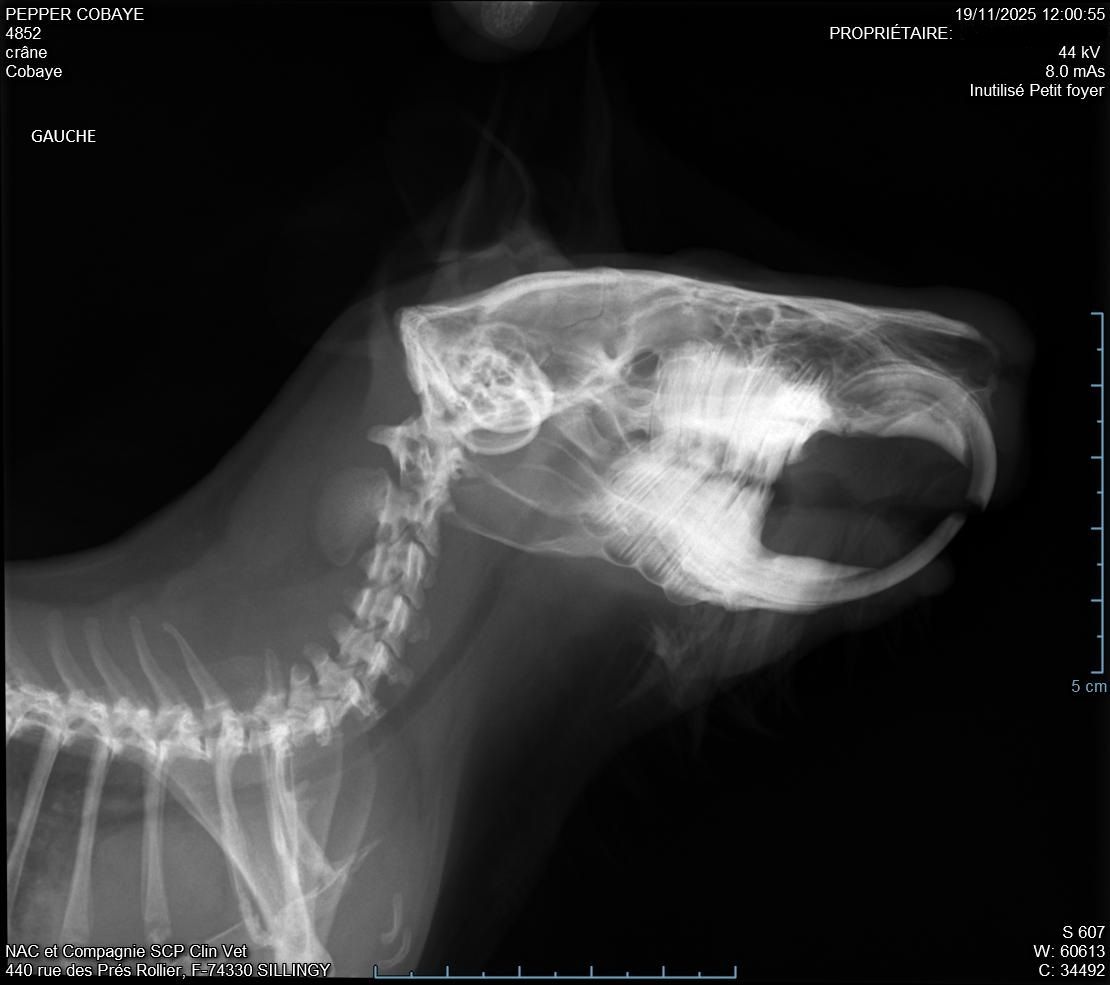

Descendu à 987g donc pas trop bougé depuis la semaine d'avant. La plaie était atone et moins belle que la semaine d'avant (pronostic pas très bon), il a fait des radios pour voir s'il n'y avait pas un problème avec ses dents mais il n'a rien vu, si pas d'amélioration il n'a pas d'autre solution. Nous somme donc repartis pour 10 jours avec un 2eme antibio en continuant le Corylap, Flagyl 125mg/ml 1ml 2x/jour + Contramal 2 à 4 gouttes 2x/jour et toujours Métacam avec le même dosage + Elugel 2x/jour sur la plaie. Changement de gavage pour Critical Care herbivore.